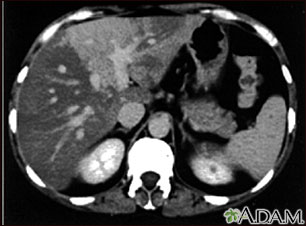

Liver with disproportional fattening, CT scan

A CT scan of the upper abdomen showing disproportional steatosis (fattening) of the liver.